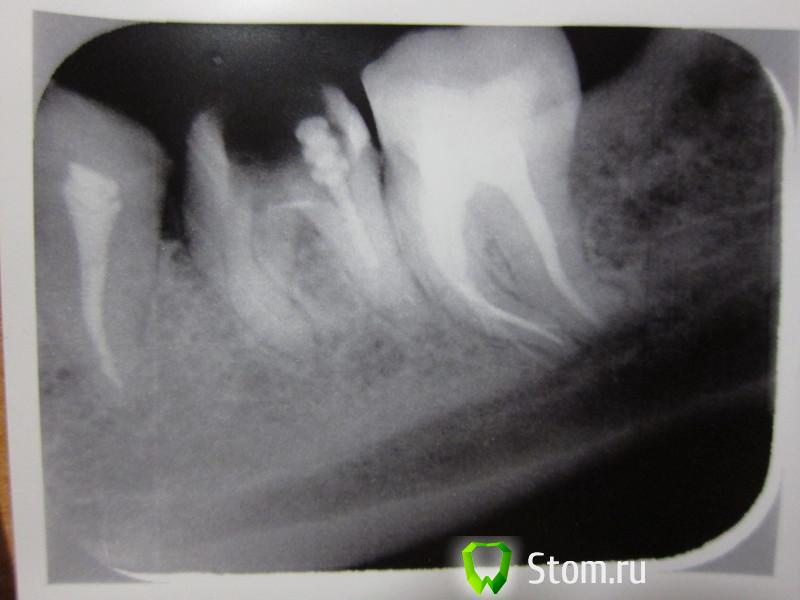

Людмила Рогозина Опубликовано 21 марта, 2012 Поделиться Опубликовано 21 марта, 2012 Помогите, нужна срочная консультация. На 37 зубе обнаружили гранулёму. История этой проблемы вкратце: в августе 2011 заболел 37 зуб - пульпит под старой пломбой - пролечили. На первых снимках никакого намёка на гранулёму! Через неделю планово удалили дистопированную ретинированную "восьмёрку" рядом - чтоб не давила на свежепролеченный зуб. Для профилактики пила линкомицин.Боли никак не проходили, при накусывании зуб сильно болел, через 5-6 недель вернулась к своему стоматологу, сделали снимок, обнаружили это затемнение поставили диагноз "периодонтит". Лечили: распломбировка, депофорез 3 раза, неделю с метапексом, затем новая пломбировка, 10 дарсонвалей, боли не утихают - инъекция преднизолона в складку, затем курс амоксиклава. Боли чуть отпустили. Первый снимок от 20 октября - сразу после перелечивания. После сняли коронку с соседнего 36, т.к. она давила на больной зуб. Через 3 месяца решила покрыть 36 зуб опять коронкой, но его перелечить не смогли, лет 15 этот "вусмерть зарезорциненный" (выражение моего врача) зуб с пустыми каналами стоял под коронкой, там каналы "застекленели". К тому же в одном из каналов там обнаружили давнишний отломок инструмента - достать, естественно, не смогли - они непроходимые вообще. Но один канал слегка расширили и установили туда анкерный штифт. Второй снимок от 3 февраля 2012 как раз по этой теме. На простых снимках врачи не видели гранулёму, говорили, что периодонтит, только на КТ обнаружили - 20 февраля. КТ выкладывать не буду, там ужасное качество, всё мелко, диска не дали, только мутные негативы, могу выложить описание (делали в ЦНИИСе - я в шоке от "качества" услуги). Суть в том, что "апикальная гранулёма визуализируется у верхушки медиально-язычного корня 37 зуба, а у 36 - разрежение костной ткани". Ортопед сказал: раз 36 перелечить не смогли - коронкой покрывать не буду. А если на 37 гранулёма, то и жалеть нечего, оба одновременно удалять и ставить импланты. С ним согласны не все специалисты. На комиссии мнения врачей разделились. Кто-то настаивал, что за гранулёмой нужно ещё минимум полгода понаблюдать, посмотреть динамику, а 36 закрыть коронкой и, когда заболит (может, даже лет через 10), удалить вместе с коронкой. 36 зуб не болит вообще и никогда не болел. 37 слегка чувствителен при прикосновении, но это не боль, а какое-то легкое "зудение", жую на нём спокойно, даже жёсткую пищу, "постанывают" иногда окружающие зуб ткани и кость под ним (или это так дырка от "восьмёрки" так заживает, не могу понять). К стоматоневрологу в МГМСУ ходила, воспаление тройничного нерва мне исключили.С хирургом тоже консультировалась - он не хочет делать резекцию, т.к. там очень близко расположен челюстной канал, опасается пареза. В гемисекции нет смысла - лучше имплантация. Реплантация - вообще экзотика. Помогите, что делать?! Можно ли попробовать под микроскопом перелечить эти несчастные 36-37 зубы в третий раз?! Или найти более смелого хирурга? Есть ли смысл в "наблюдении" за гранулёмой, вдруг начнутся осложнения? И что это за затемнение на втором снимке внизу на челюсти? На КТ мне его проигнорировали. Заранее спасибо. Ссылка на комментарий

ger_berra Опубликовано 21 марта, 2012 Поделиться Опубликовано 21 марта, 2012 Стрелкой покажите,какое затемнение Вас смущает.В 7-м похоже на сломаный инструмент в медиальном канале перфорацию.Перелечить можно попробовать 36 и 37,только с визуальным контролем(микроскоп или оптика).Если удастся распломбировать каналы,правильно отмыть и запломбировать,то прогноз благоприятный.Конечно,нужно в динамике смотреть,но только после перелечивания.Дарсонвали,уколы с десну и т.п.-это ненужные телодвижения,толку от них ноль. Ссылка на комментарий

samsonov Опубликовано 22 марта, 2012 Поделиться Опубликовано 22 марта, 2012 В 37 на дистальном ,похоже,на 2 верхушки Ссылка на комментарий